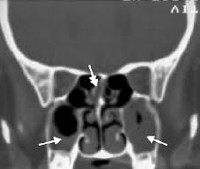

КТ ППН. Полипозный пансинусит. Отек слизистой оболочки верхнечелюстных пазух (красная стрелка), полиповидные образования в верхнечелюстных пазухах (синяя стрелка), выраженное снижение пневматизации полости носа (зеленая стрелка).

КТ ППН. Тот же пациент. Диффузное снижение пневматизации клеток этмоидного лабиринта (синяя стрелка), гиподенсивный отек слизистой оболочки клиновидных пазух (красная стрелка).

КТ ППН. Тот же пациент. Диффузное уменьшение пневматизации обоих лобных пазух, справа с включениями повышенной плотности (желтая стрелка).